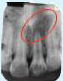

Tooth with Fracture Extending Sub-Gingivally

X-ray showing

picture line